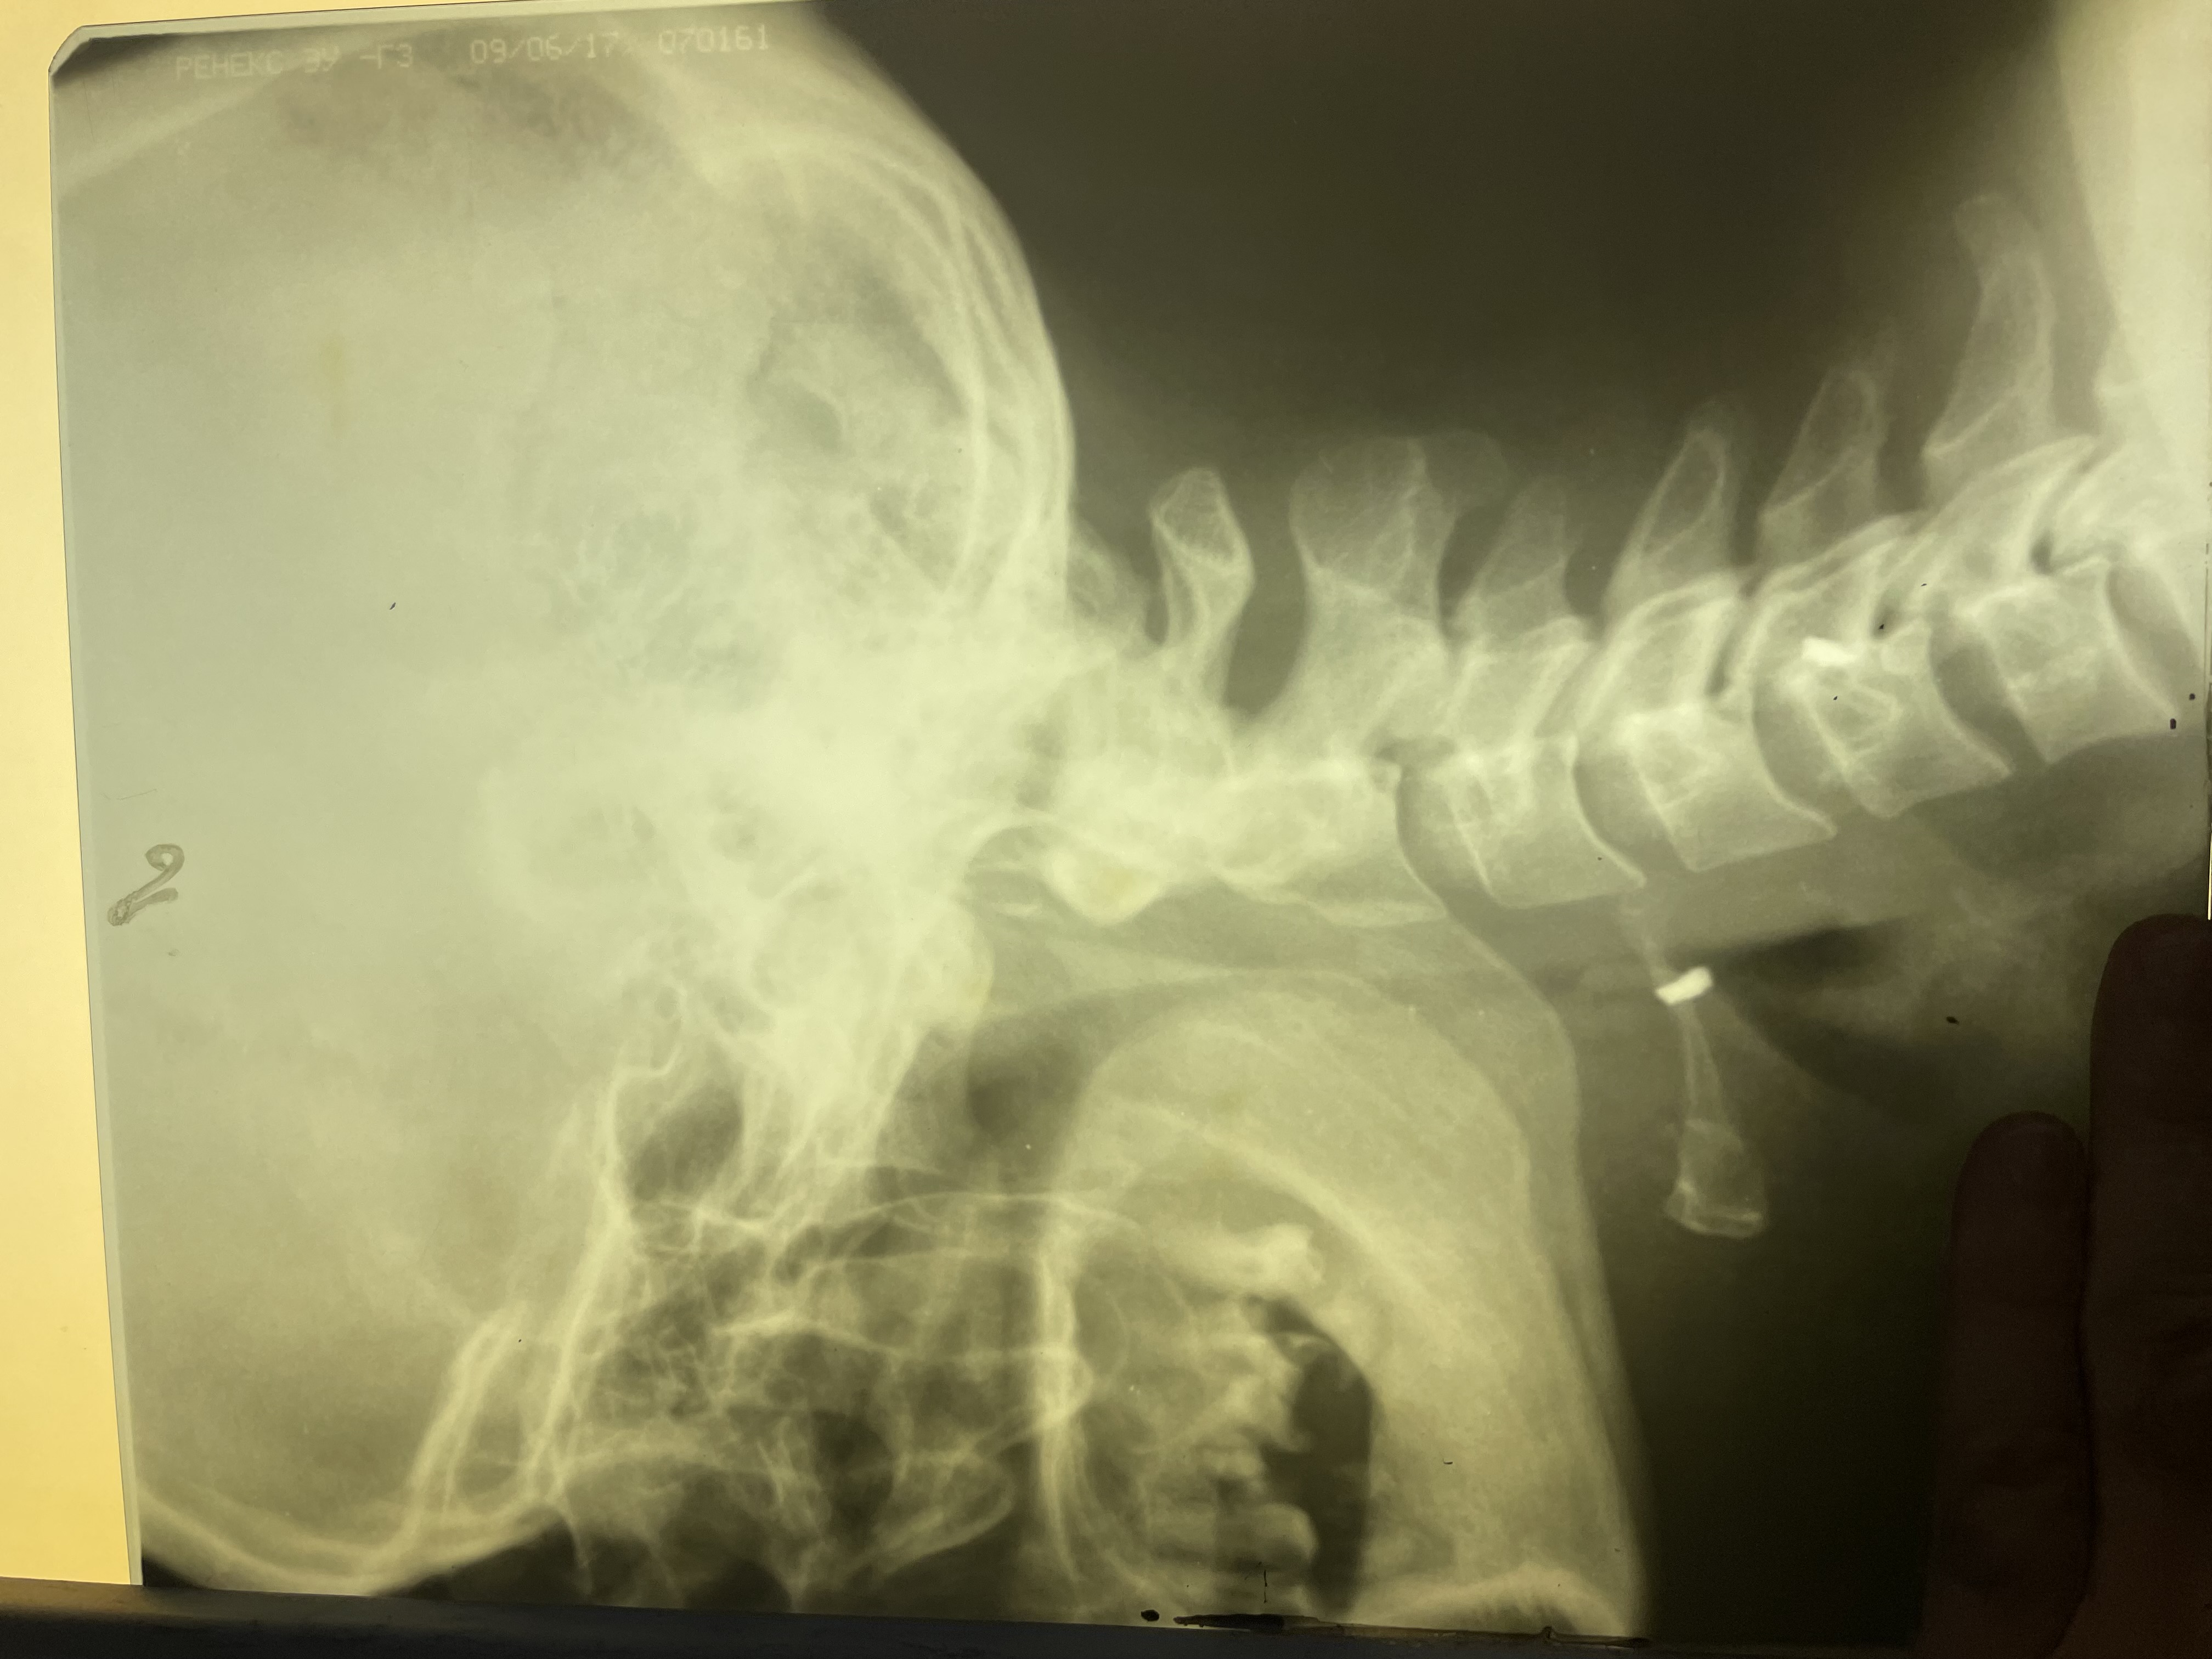

Рис. 1. Инородное тело в области подъязычной кости (рентгенограмма, боковая проекция).

Fig. 1. A foreign body in the area of the hyoid bone (X-ray, lateral projection).

На рентгенограммах шеи от 30.11.23 г. определяется ИТ в области подъязычной кости (рис 1,2).